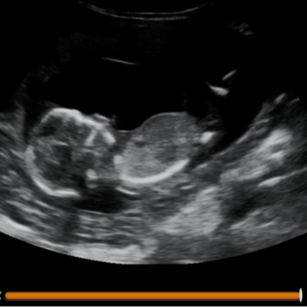

14 Weeks Pregnant

Size: ~3.4 inches (8.7 cm), the size of a Lemon!

Development Highlights:

Body grows faster than head.

Facial muscles can move; baby may make expressions.

Kidneys producing urine.

Baby’s movements more coordinated, though still not felt.